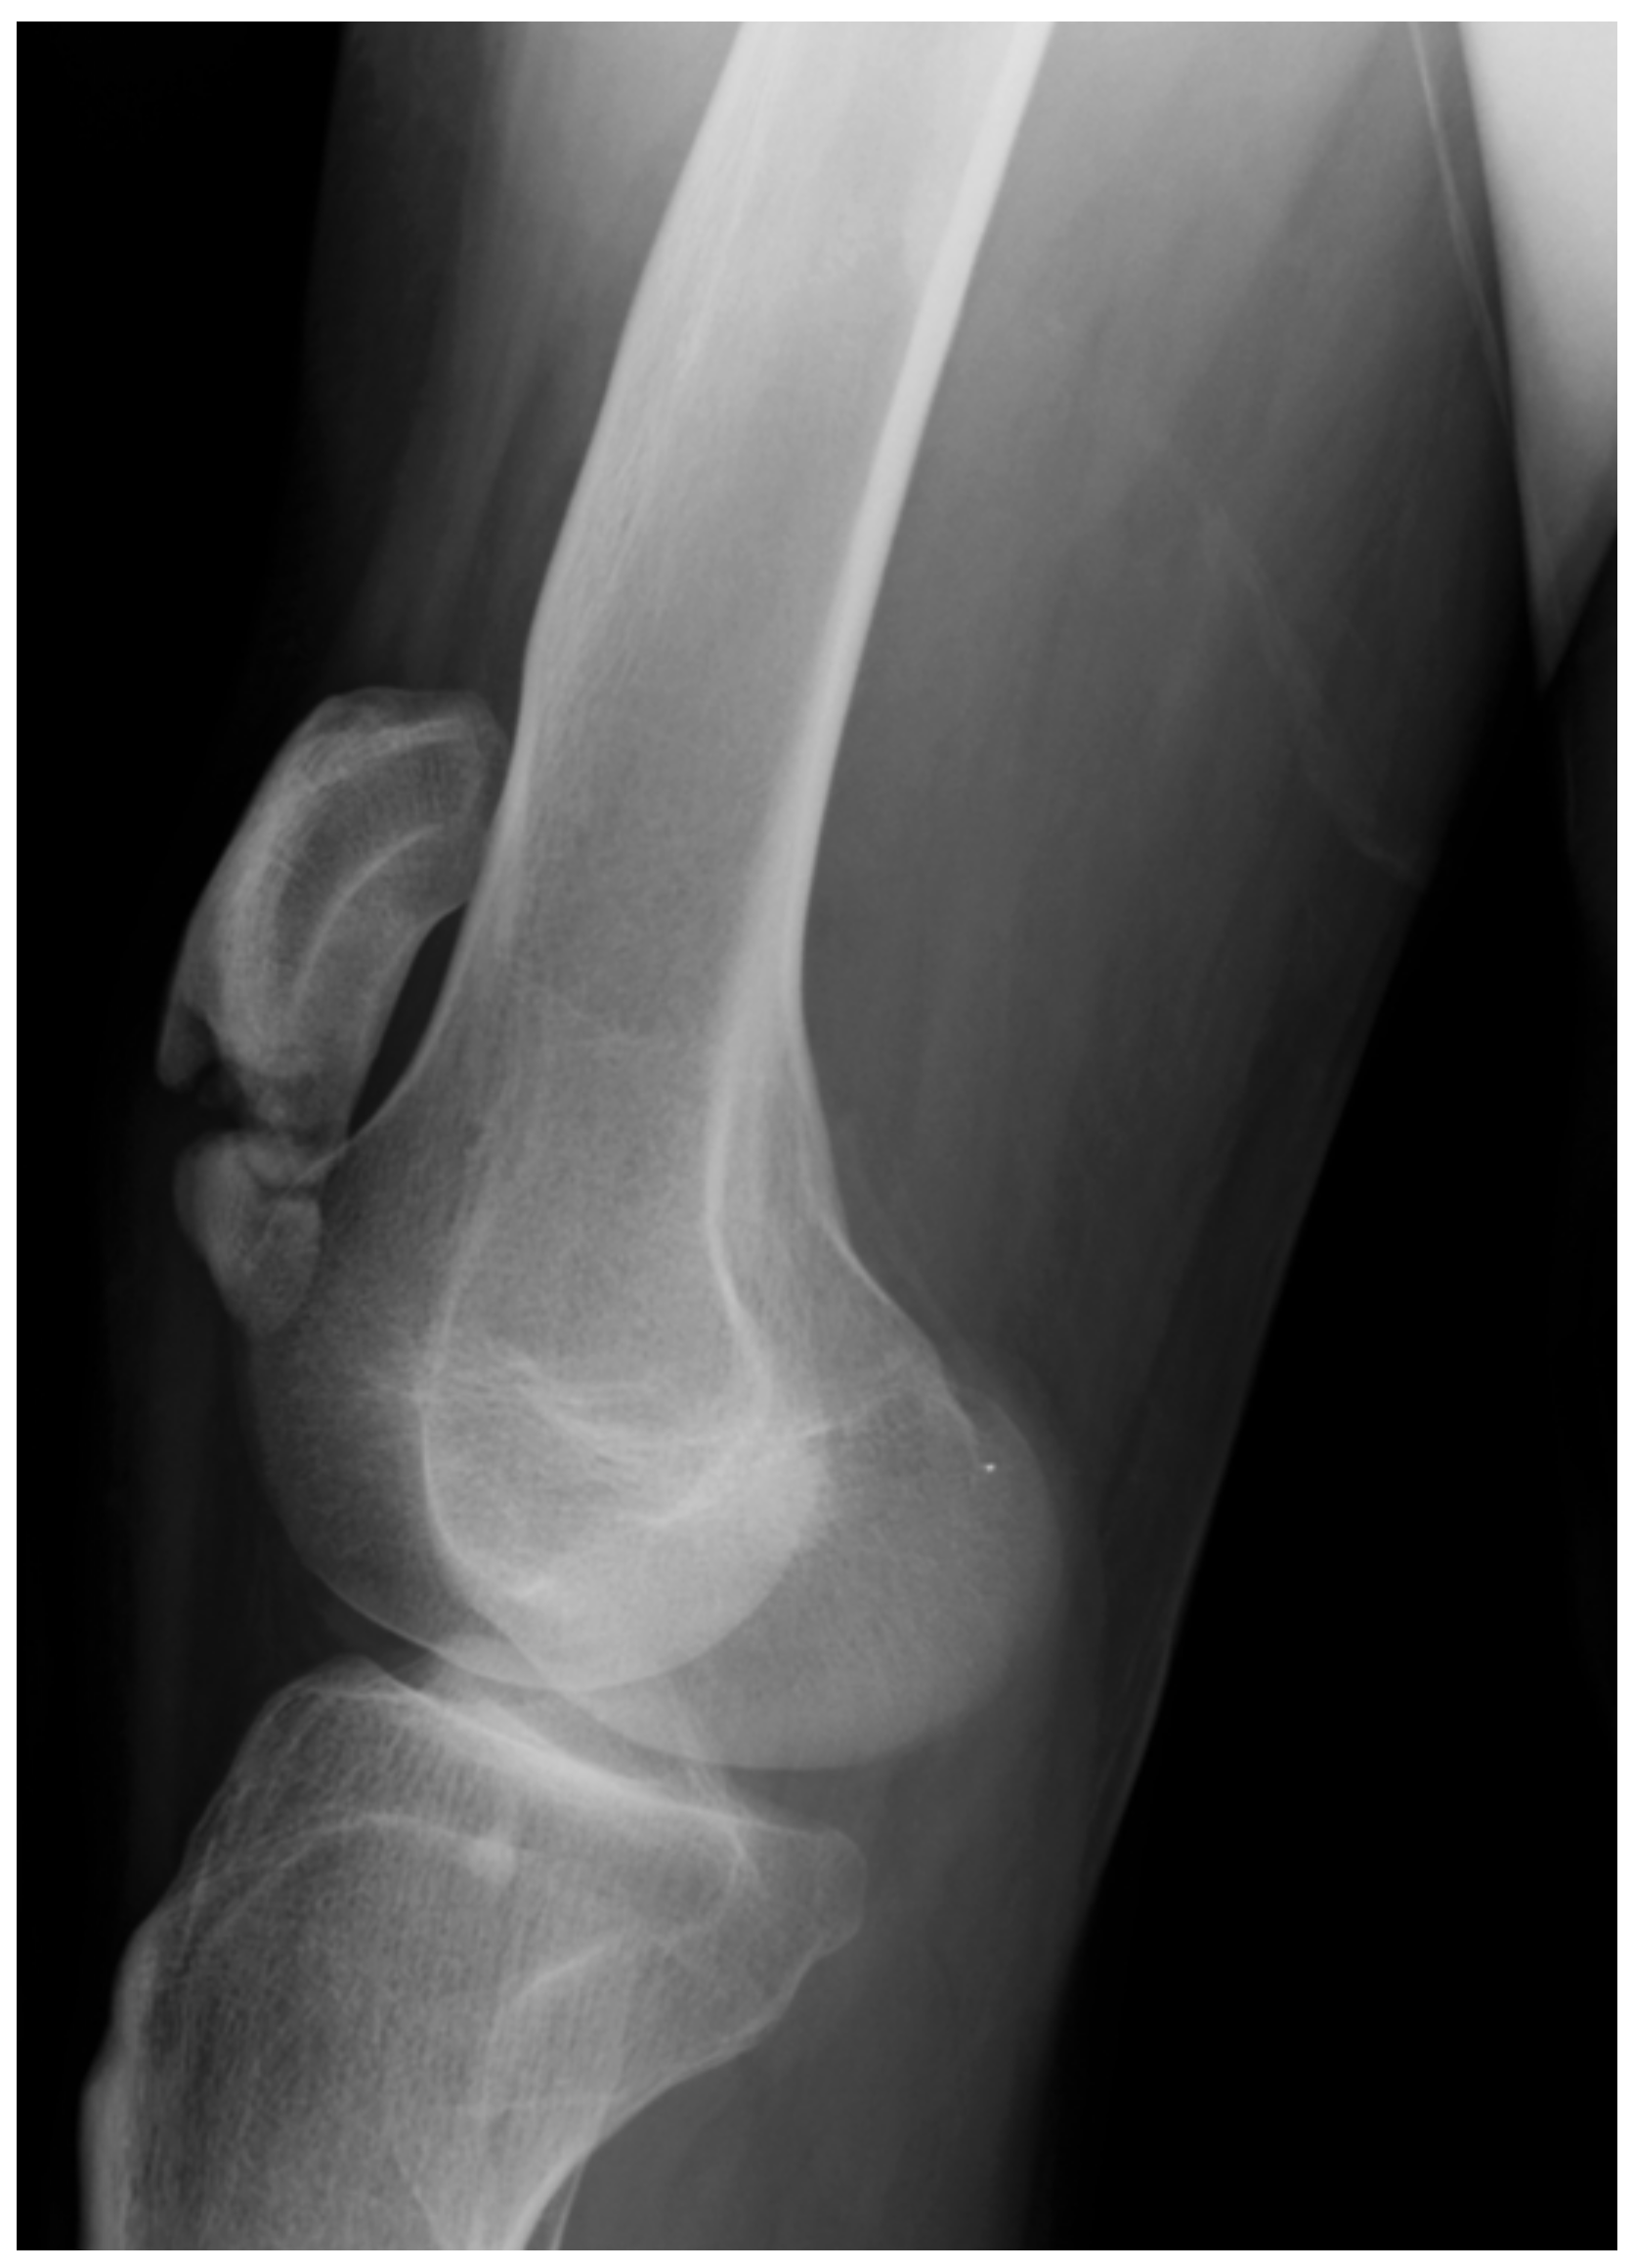

| Knee | Spastic knee flexion. Hamstring spasticity. Full knee extension and occasionally recurvatum. | Hamstring contracture. Increased popliteal angle. Full knee extension or knee FDD <10°. | Knee joint contracture. Knee FFD: <20°. Mal-alignment: FNA + ETT. Genu valgum, genu varum. | Patella alta. Knee FFD > 20°. Patella fracture/avulsion. Arthrosis. |